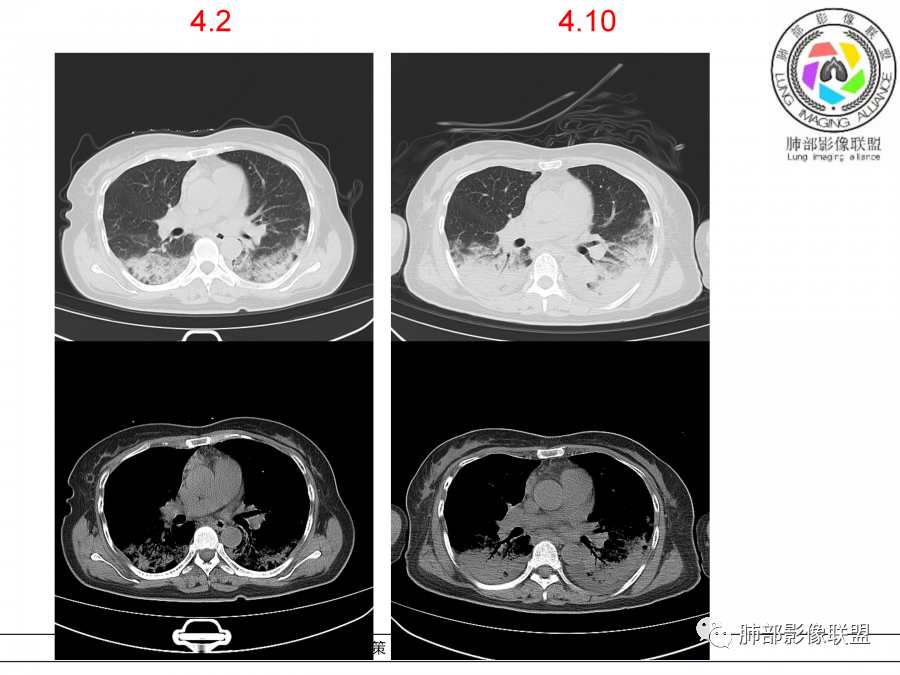

影像,第一次双肺中下叶胸膜下多发斑片状实变影,部分融合成,周围散发磨玻璃影,磨玻璃影内可见小叶间隔及小叶内间隔增厚,病变平行于胸膜,第二次间隔8天,双肺实变影明显进展,有重力作用,支气管近端堵塞,进展较快,临床有发热,血沉高,狼疮SLE阳性,考虑1:OP(机化性肺炎)2:SLE相关肺炎,建议支气管镜灌洗液病原学检测。

第一次双肺中下叶胸膜下多发斑片状磨玻璃及实变影,病变平行于胸膜,支气管通畅,8天后,双肺实变影明显进展范围扩大,部分支气管近端堵塞,进展较快,胸腔积液,抗感染治疗无效,考虑:非感染性疾病:结缔组织相关性肺病。鉴别机化性肺炎。

外围胸膜下,实变+GGO+网格,支气管通畅

提示间质为主病变

进展迅速——肿瘤就不用考虑,考虑炎性病变